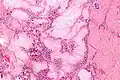

It appears that monosodium urate crystals trigger a distinct physiological NETosis pathway that coats them in DNA. These coated crystals then persist in tissues as a foreign body granuloma constituting gouty tophus.[4]